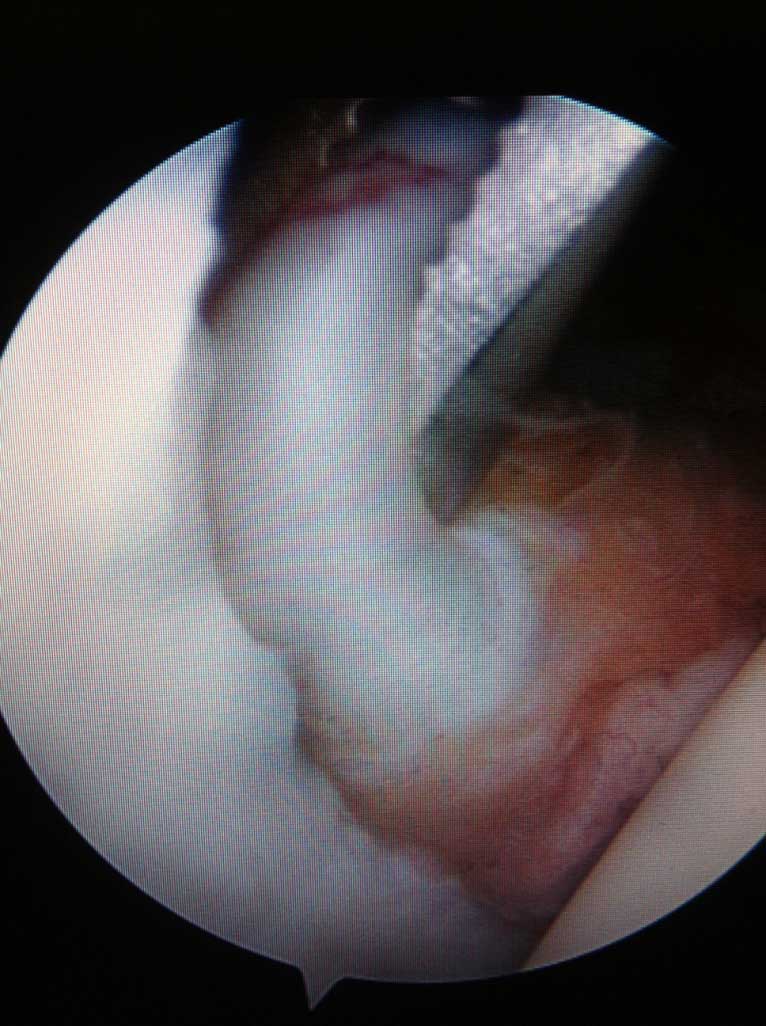

Sehnenriss

Zum Sehnenriss im Bereich der Schulter kann sowohl Unfall als auch Verschleißbedingt kommen. Kleine Risse verursachen eher Schmerzen im B. der Schulter und des Oberarmes, die grossen sind neben Schmerzen auch mit wesentlicher Kraftminderung und Beeinträchtigung der aktiven Armbeweglichkeit in der Schulter vergesellschaftet.

Wird die Indikation zur Sehnennaht / Rekonstruktion der gerissenen Sehnen gestellt, so wird die Operation in unseren Händen ausschließlich arthroskopisch (Schlüsselloch Operation) durch 3 - 6 kleinen Stichinzisionen (3-4mm) durchgeführt. Dieses operative Verfahren ist maximal zu den schulterumgebenden  Weichteilen schonend.